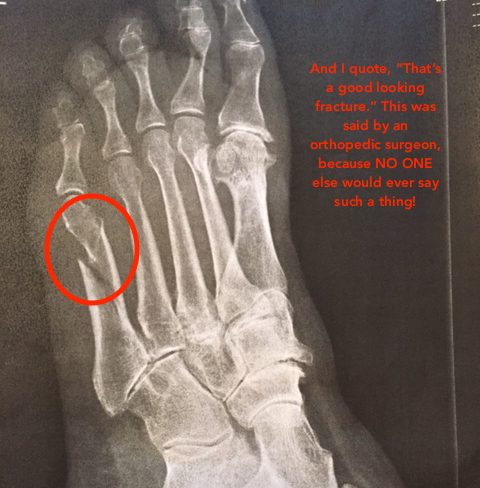

Jean was a trouper — right after it happened, she still went on a limo ride! (We hijacked the kids’ prom limo while they went to dinner — a great tip for all you parents with prom-aged children!) But, she still ended up at urgent care getting a boot and will need to see an orthopedist when she gets home. Silver lining: she’ll get to ride on one of those cool little golf carts at the airport on her way home!